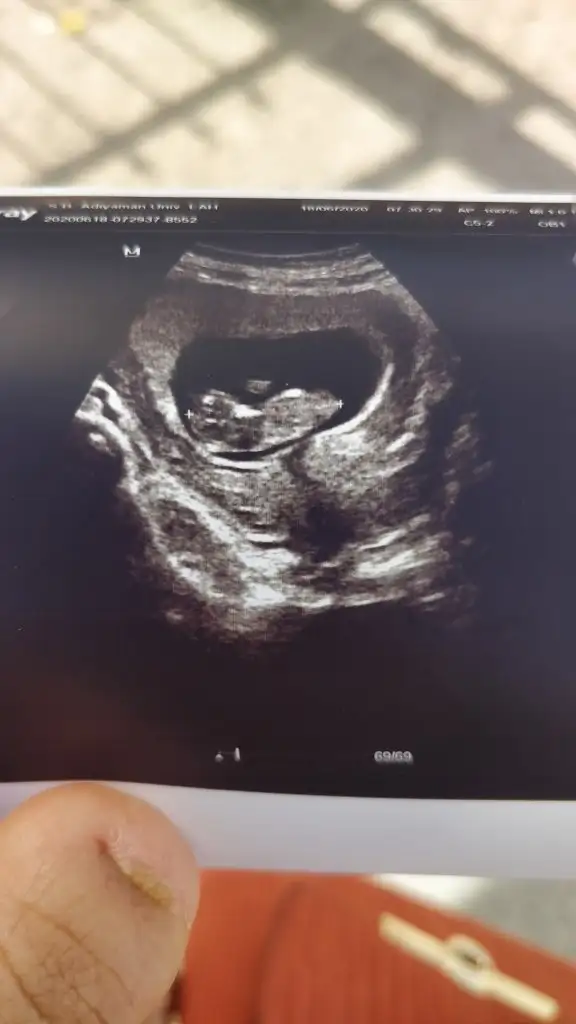

Canim 12+3 haftalık sata goreKaç haftalık usg 11 12 13 hafta olmalı sanki kız gibi

nubu görünmüyor başka usg varsa paylaşın 11 12 13 haftalar olabilirSizce kız mı erkek mi bana paralel gibi göründü Eki Görüntüle 2650002

13 haftaya yarın giriyorum doktorum 27sinde gel cinsiyet için dedi canım bakalım o gün göstermezse tekrar usg paylaşırımnubu görünmüyor başka usg varsa paylaşın 11 12 13 haftalar olabilir